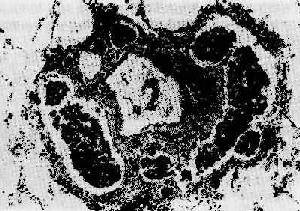

二、肿瘤的生长方式和扩散1.肿瘤的生长速度 各种肿瘤的生长速度有极大的差异,主要决定于肿瘤细胞的分化成熟程度。一般来讲,成熟程度高、分化好的良性肿瘤生长较缓慢,几年甚至几十年。如果其生长速度突然加快,就要考虑发生恶性转变的可能。成熟程度低、分化差的恶性肿瘤生长较快,短期内即可形成明显的肿块,并且由于血管形成及营养供应相对不足,易发生坏死,出血等继发改变。 (1)膨胀性生长:这是大多数良性肿瘤所表现的生长方式。由于这种瘤细胞生长缓慢,不侵袭周围正常组织,随着肿瘤体积的逐渐增大,有如逐渐膨胀的气球,向四周组织推挤。因此肿瘤往往呈结节状,周围常有完整的包膜,与周围组织分界清楚(图7-3)。位于皮下者临床触诊时可以推动,容易手术摘除,摘除后也不易复发。虽这种生长方式的肿瘤对局部器官、组织的影响主要为挤压或阻塞,一般均不明显破坏器官的结构和功能。

肿瘤呈卵圆形,有包膜,与周围肾上腺组织分界清楚 (2)外生性生长:发生在体表、体腔表面或管道器官(如消化道,泌尿生殖道等)表面的肿瘤,常向表面生长,形成突起的乳头状、息肉状、蕈状或菜花状的肿物。这种生长方式称为外生性生长。良性肿瘤和恶性肿瘤都可呈外生性生长。但恶性肿瘤在外生性生长的同时,其基底部往往也呈浸润性生长,又由于其生长迅速,血液供应不足,这种外生性肿物容易发生坏死脱落而形成底部高低不平、边缘隆起的癌性溃疡。 (3)浸润性生长:为大多数恶性肿瘤的生长方式。瘤细胞分裂增生,侵入周围组织间隙、淋巴管或血管内,如树根之长入泥土,浸润并破坏周围组织。因而此类肿瘤没有包膜,与邻近的正常组织紧密连接在一起而无明显界限(图7-4)。临床触诊时,肿瘤固定不活动。手术切除这种肿瘤时,切除范围比肉眼所见肿瘤范围为大,因为这些部位也可能有肿瘤细胞的浸润。